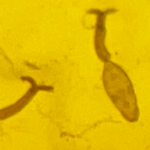

日本血吸虫尾蚴(图源:中国疾控中心)

其中,尾蚴是可以感染人体的阶段,虫卵孵化成毛蚴后钻入钉螺中,再由钉螺释放大量尾蚴到水中,使含有尾蚴的水体成为“疫水”。

人如果接触了含有血吸虫尾蚴的水体——“疫水”,只需短短10秒,尾蚴就会迅速从皮肤钻入人体内致人感染。